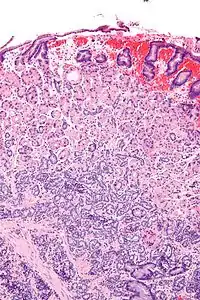

![]() Гістопатологічний знімок нейроендокринної пухлини шлунка. Гістопатологічний знімок нейроендокринної пухлини шлунка. | |